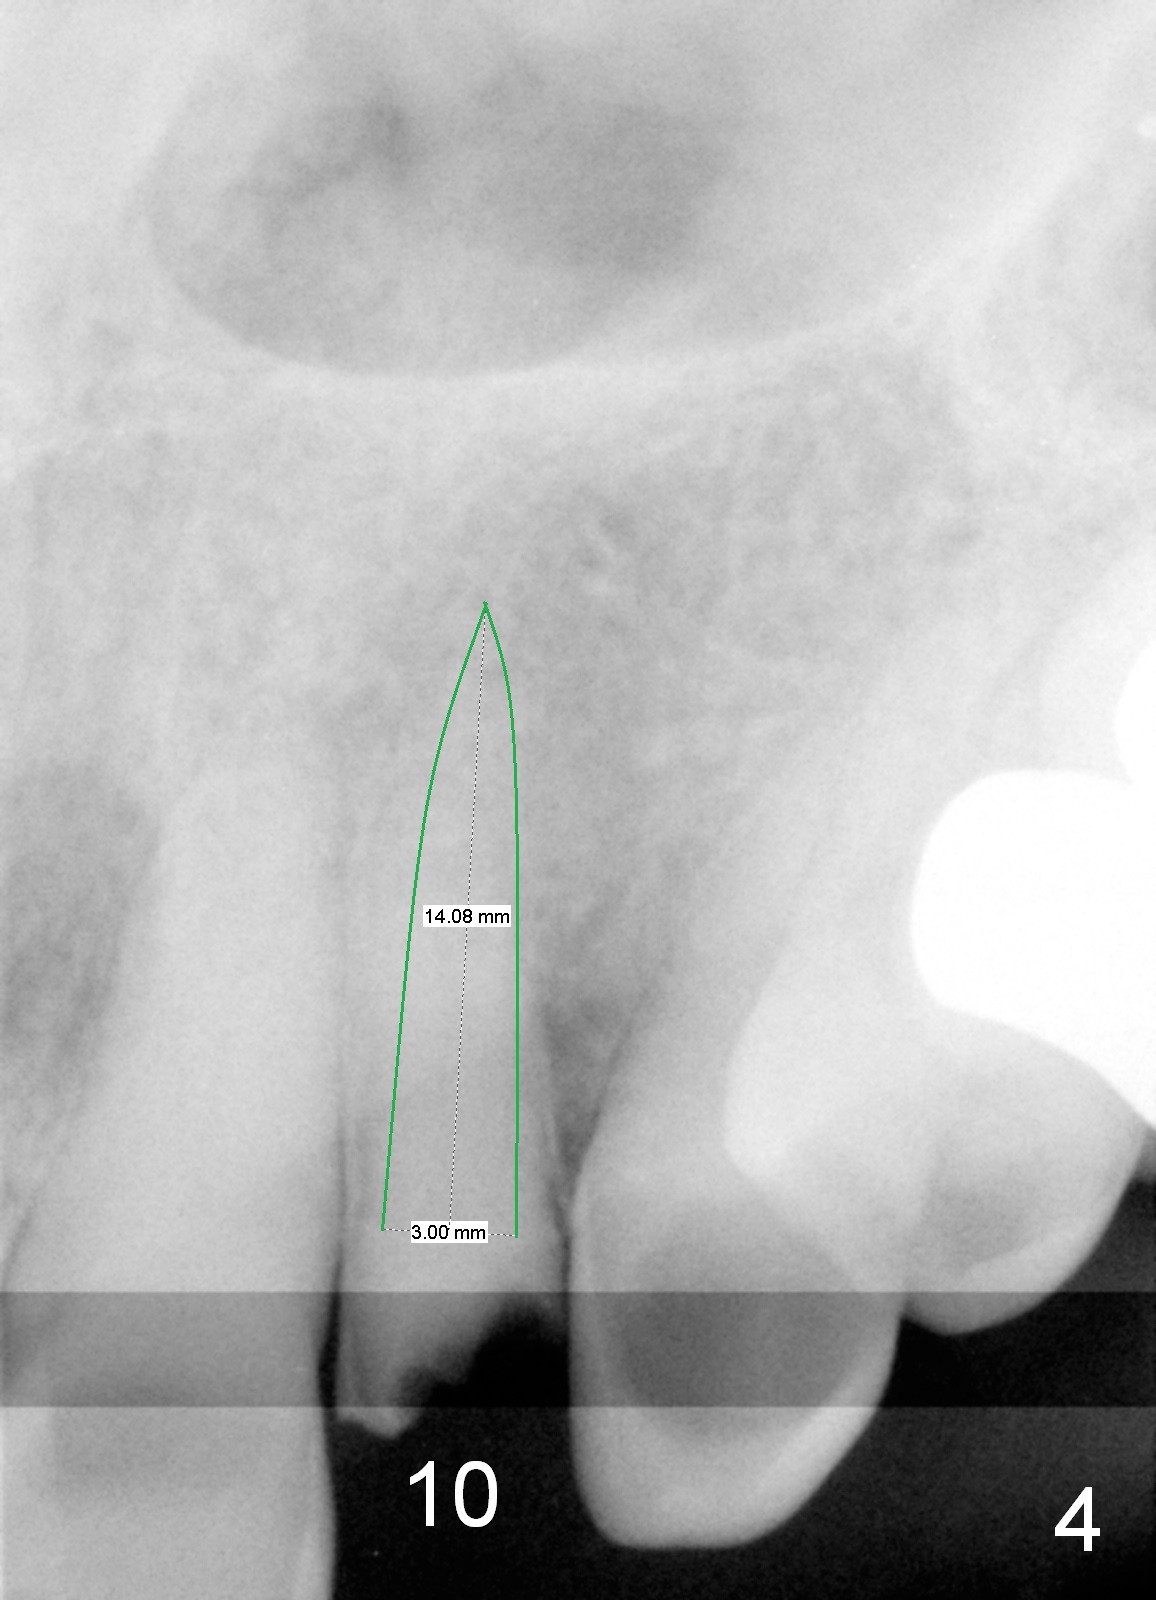

A 88-year-old man (CA) has severe xerostomia-induced caries. After caries control, implants will be placed at #7, 8 and 10 with narrow mesiodistal width (Fig.1,2). Note concavity at the apical buccal plate (*). To prevent perforation, an angled 1-piece implant will be used at #7. Try to place the implant in the middle of the alveolus (digital palpation while drilling) and let the angled abutment take care of the trajectory. To preserve papillae, flapless approach is going to be adopted. Initial depth at these sites will be 12,14 and 14 mm, respectively (Fig.3,4). Use Boley gauge to measure widths of the root to determine the diameter of the implant.